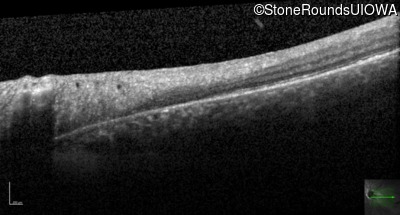

Optical Coherence Tomography - Left - 20/32 -1

Exemplar / OCT Stack

Optical Coherence Tomography - Left - 20/32 +1